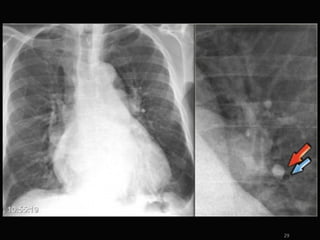

Initial Presentation

specifisc